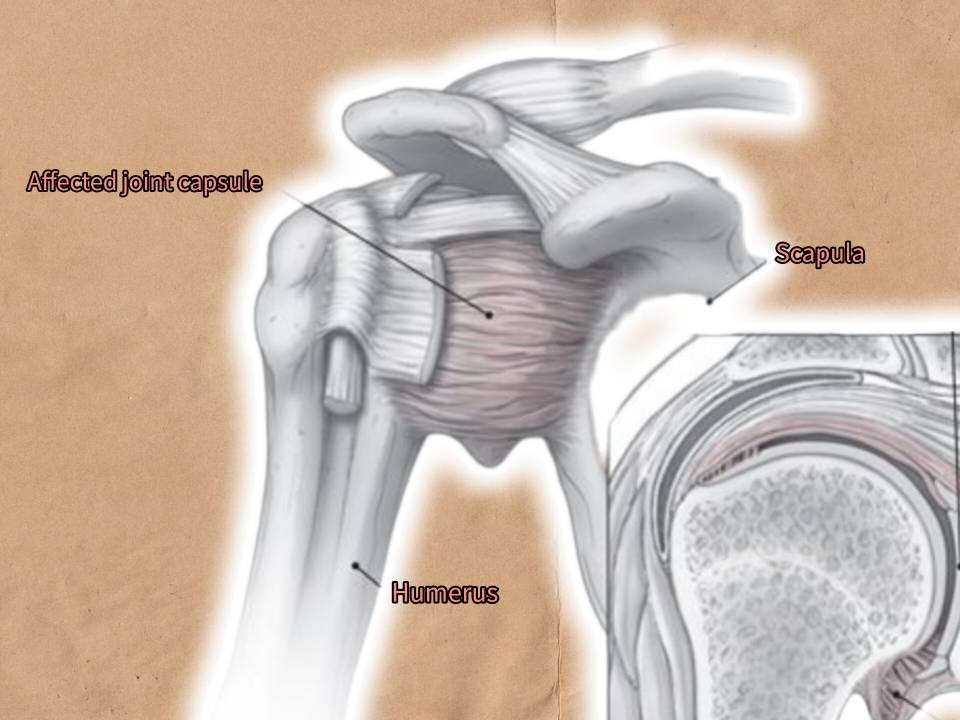

یک التهاب غیر عفونی با چسبندگی کپسول شانه است به طوری که همراه با درد، سفتی و محدودیت حرکتی می باشد. هم چنین می تواند منجر به خشکی شانه شود. فرد به طور تدریجی دامنه حرکتی خود را از دست می دهد. و علائم می تواند شدت بیشتری پیدا کند. در بیشتر موارد این بیماری، همراه با دیابت و سایر درگیری های شانه دیده می شود. کپسولیت چسبنده نام دیگر این بیماری است.

علائم این بیماری در چند ماه خود را نشان می دهد. در برخی از بیماران منجر به اختلال خواب می شود به طوری که در شب ها تشدید پیدا ورده و فرد از خواب می پرد. کم شدن محدوده حرکتی بارزترین نشانه این بیماری است. در این بیماری، کپسول شانه ملتهب شده و دچار زخم می شود. این التهاب و زخم منجر به کاهش دامنه حرکتی و سفتی در ناحیه می شود. علائم در طول زمان تشدید می یابد و همراه با سوزش خواهد بود. بالا آوردن دست و بردن آن به پشت به تدریج مشکل می شود. به طور کلی علائم شانه یخ زده را به 3 مرحله تقسیم می کنیم:

در شانه یخ زده، کپسول ملتهب شده و ضخیم می شود به طوری که فضای مفصلی کم می شود.